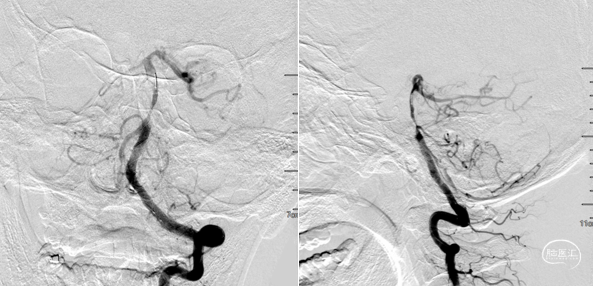

AXS Infinity导管鞘结合AXS Catalyst 7颅内支持导管,导管鞘支撑裸奔到位,抽吸10s后明显落空,大量血栓。

AXS Infinity LS导管鞘结合AXS Catalyst 7颅内支持导管。导管鞘支撑,颅内支持导管送至基底动脉远端再次抽吸,多次抽吸无负压后结束抽吸 。

抽吸再通后造影,近端残余明显狭窄且局部毛糙,拟支架成型。

3.0*8 mm球扩支架,小压力,减少穿支损伤。

支架后造影